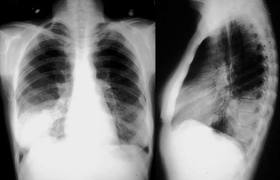

Relación entre los resultados de la radiografía de tórax y el inicio del tratamiento antibiótico en el tratamiento de la neumonía adquirida en la comunidad por médicos generales

En los pacientes con sospecha de neumonía adquirida en la comunidad (NAC), los médicos de cabecera tuvieron sistemáticamente en cuenta los resultados de las pruebas de respuesta positiva para iniciar el tratamiento antibiótico y tuvieron mucho menos en cuenta las pruebas de respuesta negativa. Estos resultados justifican la aclaración de qué se debe hacer en los casos de sospecha clínica de NAC sin confirmación radiológica. The Annals of Family Medicine, noviembre de 2024,